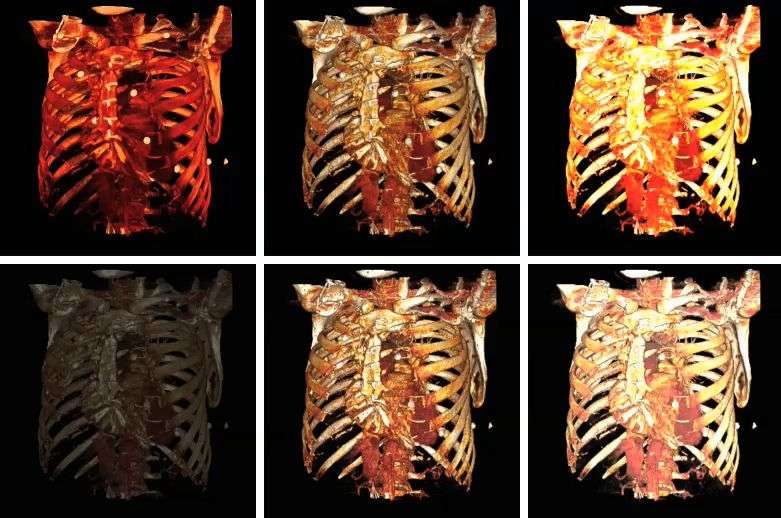

The influence on volume rendering of various shading settings is shown below:

The shading settings used for the above images are as follows:

| Image | Ambient Coefficient | Diffuse Coefficient | Specular Coefficient | Specular Power |

|---|---|---|---|---|

| Top Left | |

|

|

|

| Top Middle | |

|

|

|

| Top Right | |

|

|

|

| Bottom Left | |

|

|

|

| Bottom Middle | |

|

|

|

| Bottom Right | |

|

|

|